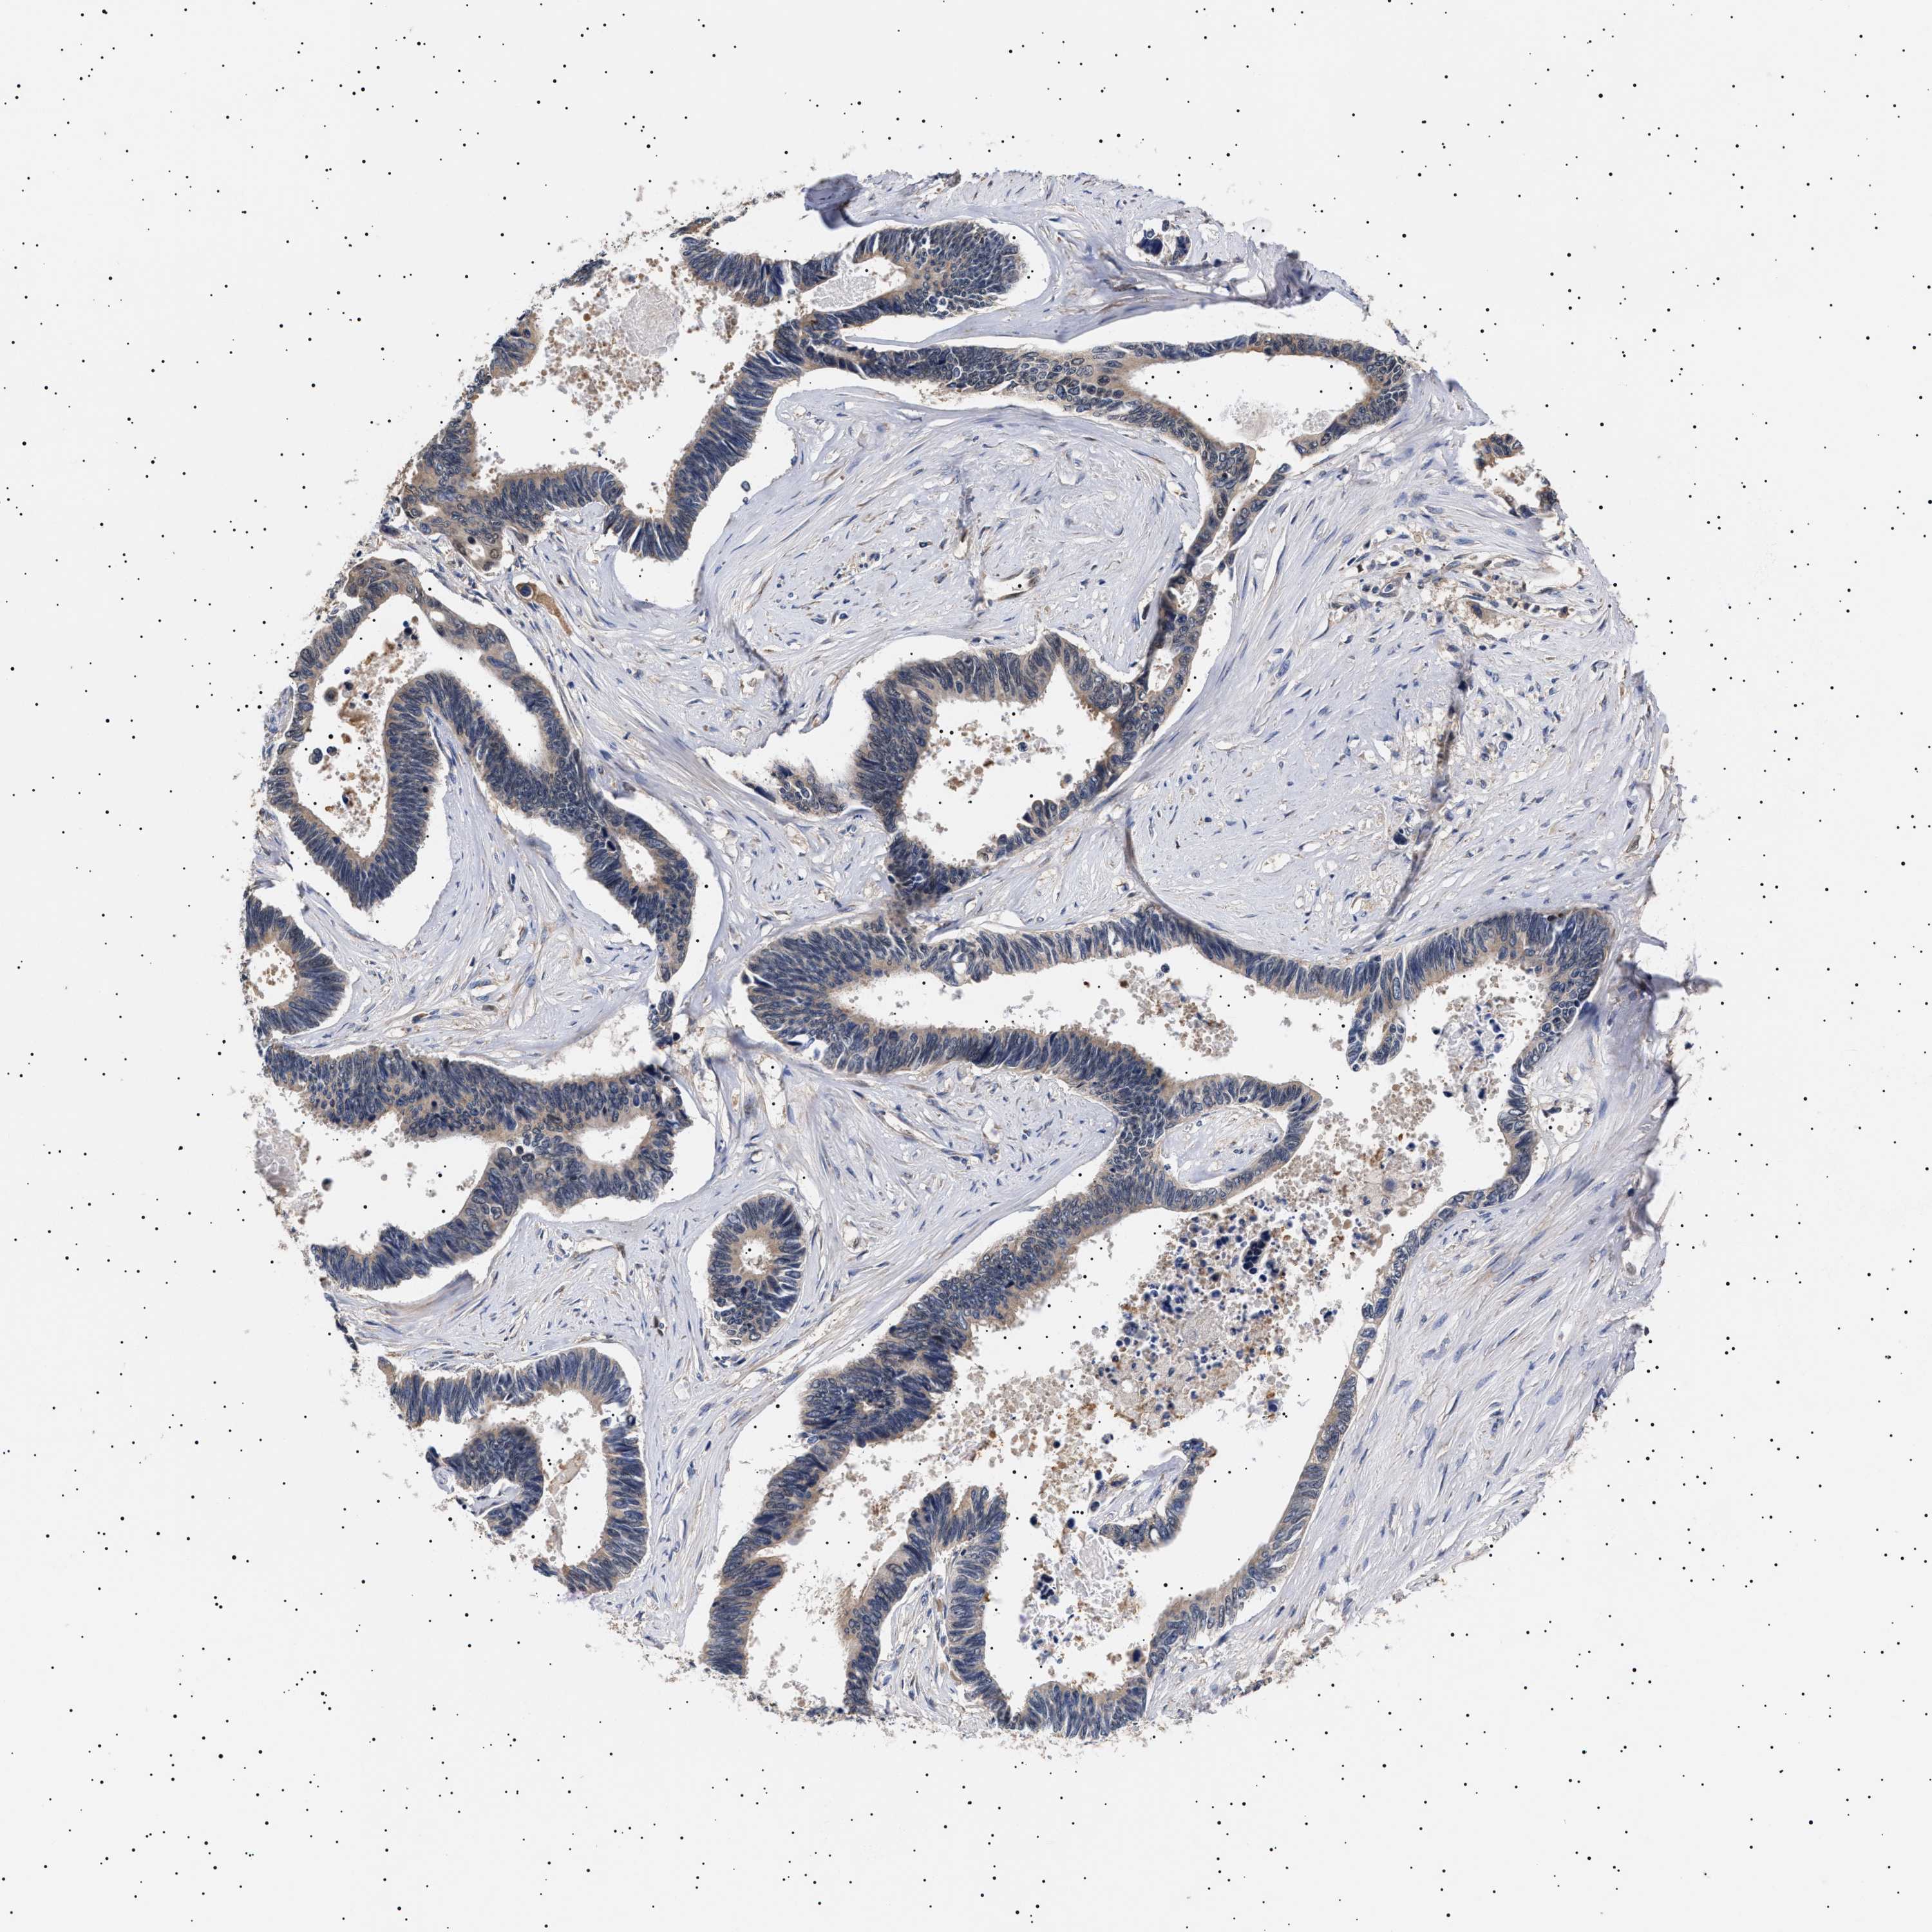

PANCREATIC CANCER - Protein expressioni

A mouse-over function shows sample information and annotation data. Click on an image to view it in a full screen mode. Samples can be filtered based on level of antibody staining by selecting one or several of the following categories: high, medium, low and not detected. The assay and annotation is described here.

Note that samples used for immunohistochemistry by the Human Protein Atlas do not correspond to samples in the TCGA dataset.

Antibody stainingi

Antibody staining in the annotated cell types in the current human tissue is reported as not detected, low, medium, or high, based on conventional immunohistochemistry profiling in selected tissues. This score is based on the combination of the staining intensity and fraction of stained cells.

Each image is clickable and will lead to virtual microscopy that enables deeper exploration of all samples and also displays staining intensity scores, fraction scores and subcellular localization as well as patient and tissue information for each sample.

Antibody HPA021237

Antibody HPA050448

Adenocarcinoma, NOS